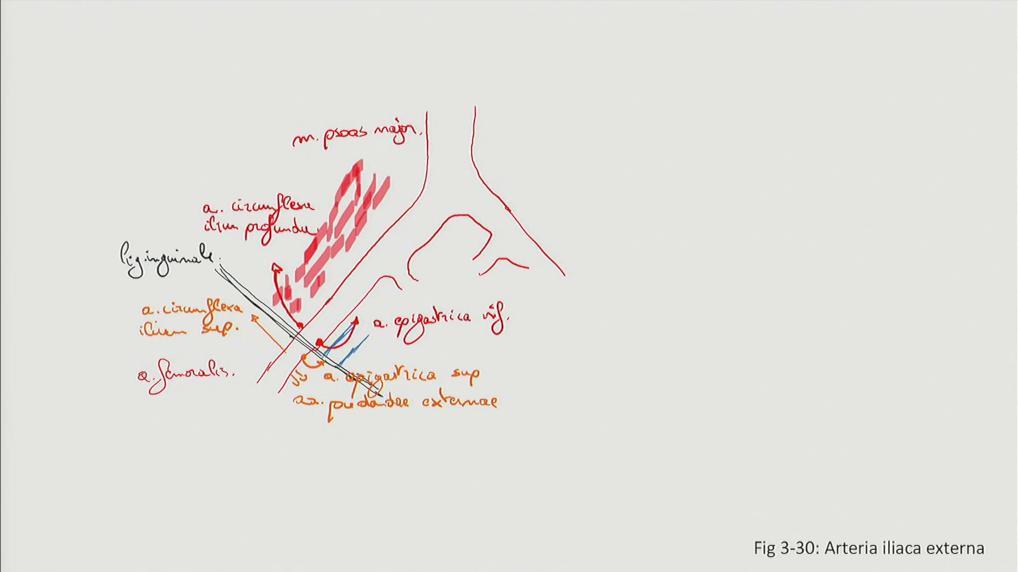

Fig 3.30: a. iliaca externa

|

Sobotta: Fig 4.155